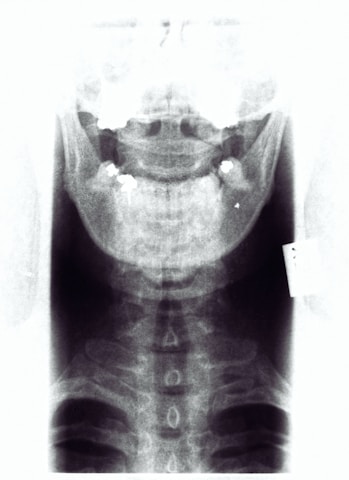

¿Por qué los quiroprácticos usan radiografías?

Ver es saber, no ver es adivinar. En Freedom Quiropráctica no adivinamos cuando se trata de tu salud. Las radiografías proporcionan información valiosa sobre la estructura y alineación de la columna vertebral, pueden revelar fusiones vertebrales, fracturas antiguas o anomalías estructurales en la columna vertebral que no son evidentes mediante un examen físico.

Las radiografías pueden ayudar a descartar condiciones médicas más graves que podrían requerir la atención de otros profesionales de la salud. Esto es crucial para garantizar que recibas la atención adecuada, personalizar el cuidado quiropráctico y realizar ajustes específicos.